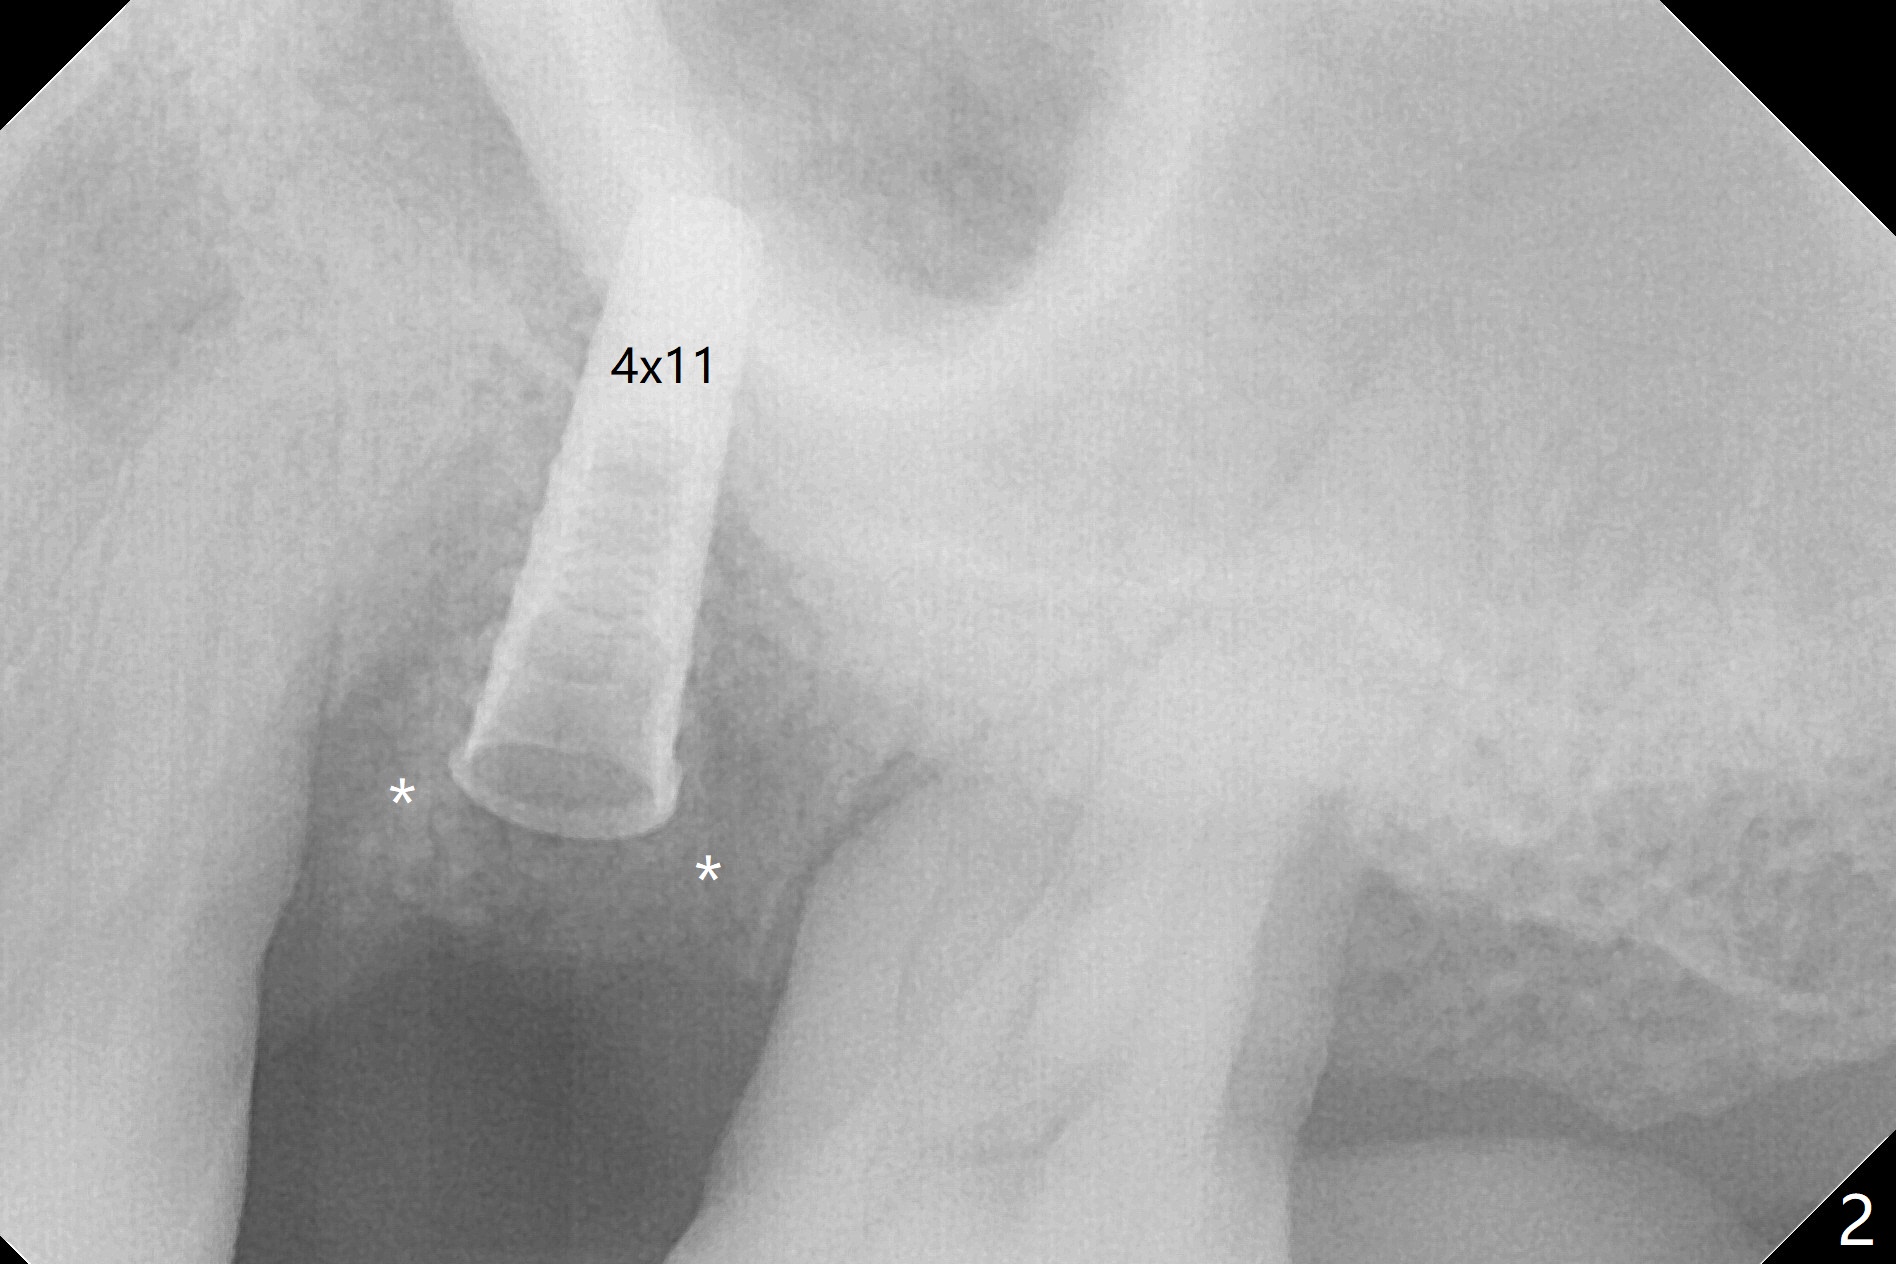

Osteotomy is initiated with Magic Split and 3 mm Magic Expander (ME, flapless) nearly 3 months post socket preservation. To improve the trajectory, the ME is redirected (Fig.1 red line). After use of 3.8 mm ME, Vanilla Graft is placed in the buccal and mesial aspects of the osteotomy. Following reuse of 3 and 3.8 mm MEs, a 4x11 mm dummy implant is inserted with stability (Fig.2 (*: allograft)). More of allograft is placed prior to placement of 5x11 mm IBS implant (Fig.3,4 (~30 Ncm)). The latter is placed palatal. Last the allograft is placed palatal. A 5x4(2) mm abutment is placed to hold periodontal dressing in place. When the ridge is narrow, the implant should be small; 4 mm probably the most appropriate in this case. There is a buccal gap 2 weeks postop (i.e., after dislodgement of periodontal dressing, Fig.5). The implant and abutment appear to be loose ~ 1.5 months postop. The pair abutment is changed to a healing one (5x3mm). The implant seems to be osteotointegrated 3.5 months posotp (Fig.6). Because of the mesial shift of the tooth #15 (Fig.6 arrow (6 months post #14 extraction; anterior open bite)), an angled abutment (5x4mm, 15 degree) is used (Fig.7). Limited orthodontic treatment has to be initiated because the mesially shifted #15 has no occlusal contact mesially (Fig.7 *). A provisional is fabricated with light supra-occlusion. A separator is placed between #14 and 15. Once a space is created in a week, acrylic is added to the distal surface of the provisional and the separator is re-used. In fact the implant is found to be unstable 4.5 months postop (Fig.8,9). The palatal (P) plate is thin and incomplete. The provisional is reduced infraocclusal. Two months the implant remains unstable and is removed.